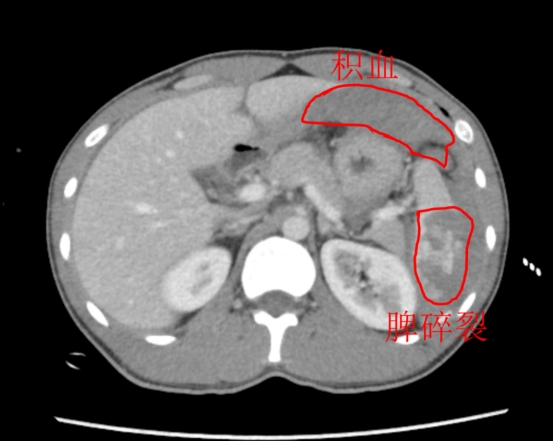

值班医生立即采取措施:抽血、建立多重静脉通道、紧急备血、推入CT室……当增强CT报告呈现在眼前时,急诊增强CT报告:脾破裂;脾周、肝周及腹盆腔大量积血,AAST分级为Ⅳ级,是极其严重的脾破裂。

腹腔镜镜头下展现的是一片“血海”:脾脏下极严重破裂,鲜血仍在汩汩涌出。巨大的出血量和有限的操作空间,考验着术者的沉着与技艺。